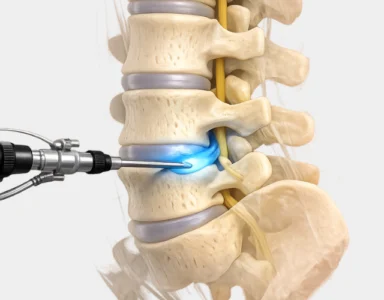

"These days, I always recommend endoscopic spine surgery to my patients. It is a modern and minimally invasive approach. The incisions are smaller. The blood loss is minimal. And the recovery is much faster compared to traditional spine surgery. The results are far better. Patients are back on their feet sooner. And the risk of complications is also lower.

At Aditya Hospital, we are proud to be the only hospital in Rewari offering endoscopic spine surgery. Our patients deserve the best. And we are committed to giving them exactly that."